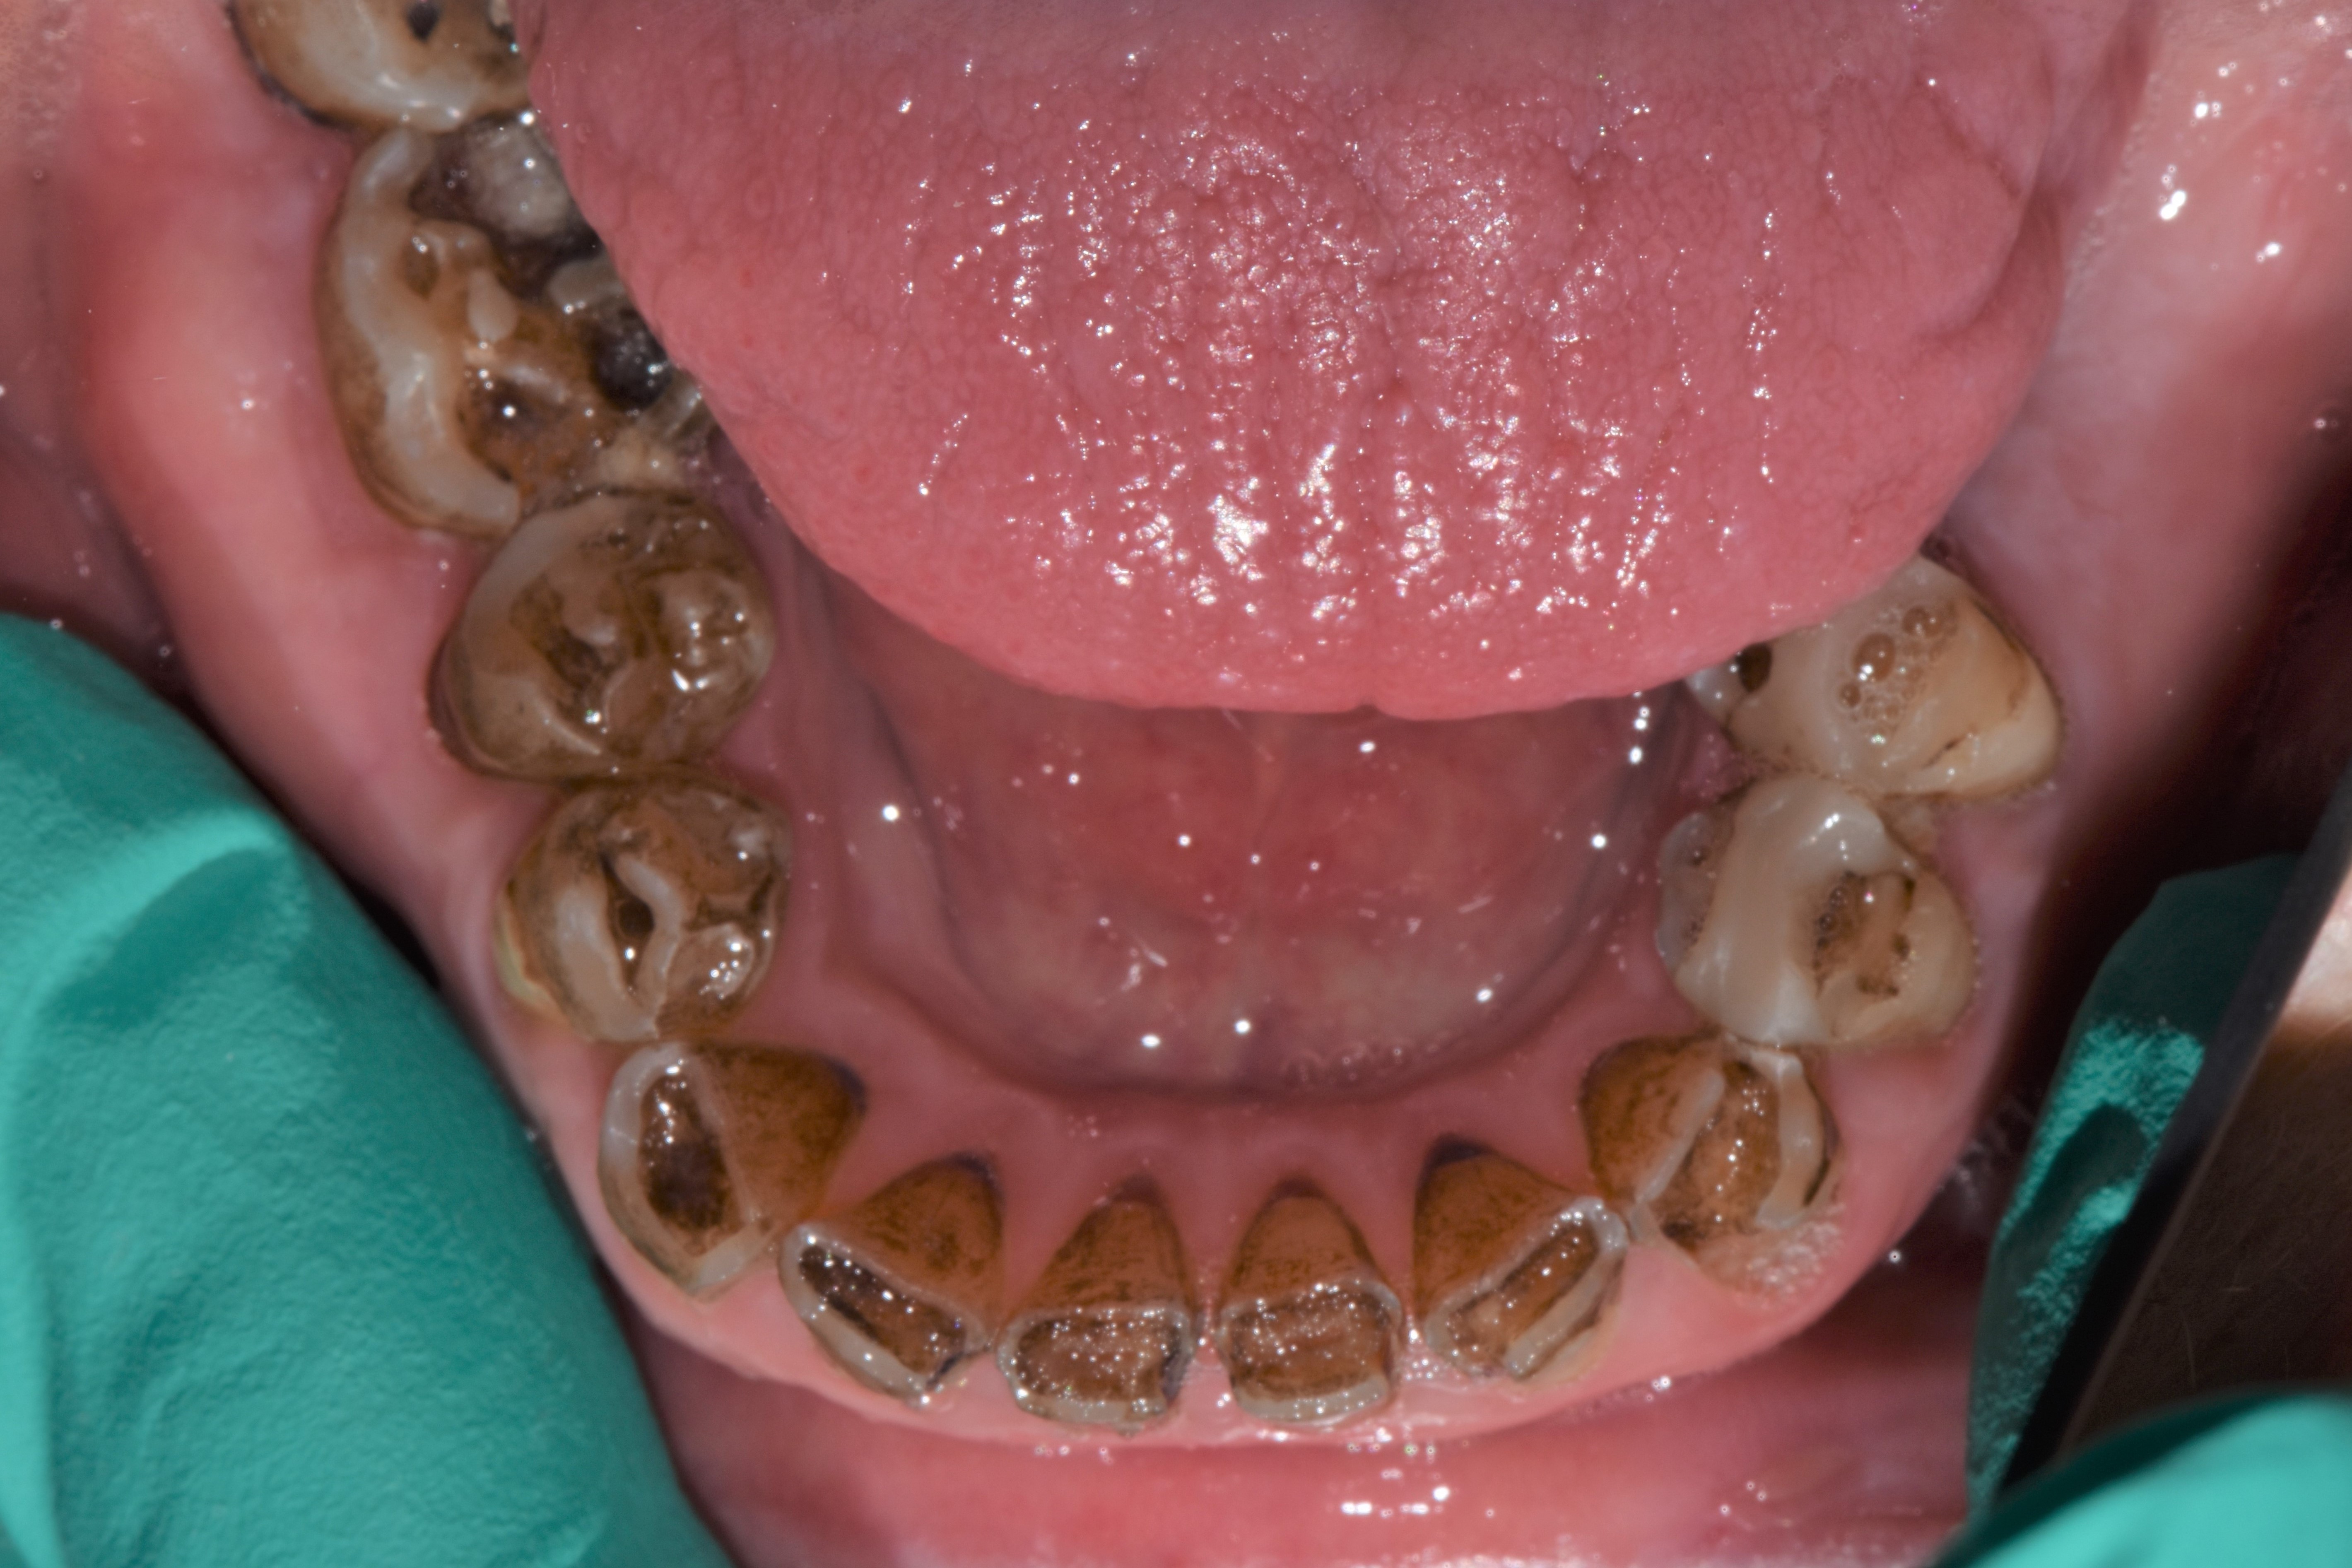

At a clinic treating patients in an underserved population, a 54-year-old female patient presented requesting extraction of all of her teeth and fabrication of dentures for her long-term restorations. The patient had a history of breast cancer, which had been treated with chemotherapy. She believed that full dentures would be an appropriate treatment option for her, owing to the poor state of her oral health and dentition and because she had limited financial resources and did not think that she could afford restoration of her teeth. The patient reported that she had experienced depression and alcohol abuse because of her cancer diagnosis, and that she had neglected her dental care during the course of her cancer treatment, resulting in generalized moderate-to-severe caries with moderate wear due to bruxism (Figure 1 through Figure 5). She also presented with significant staining of her remaining dentition due to the alcohol abuse.

Fig. 3

Fig. 4